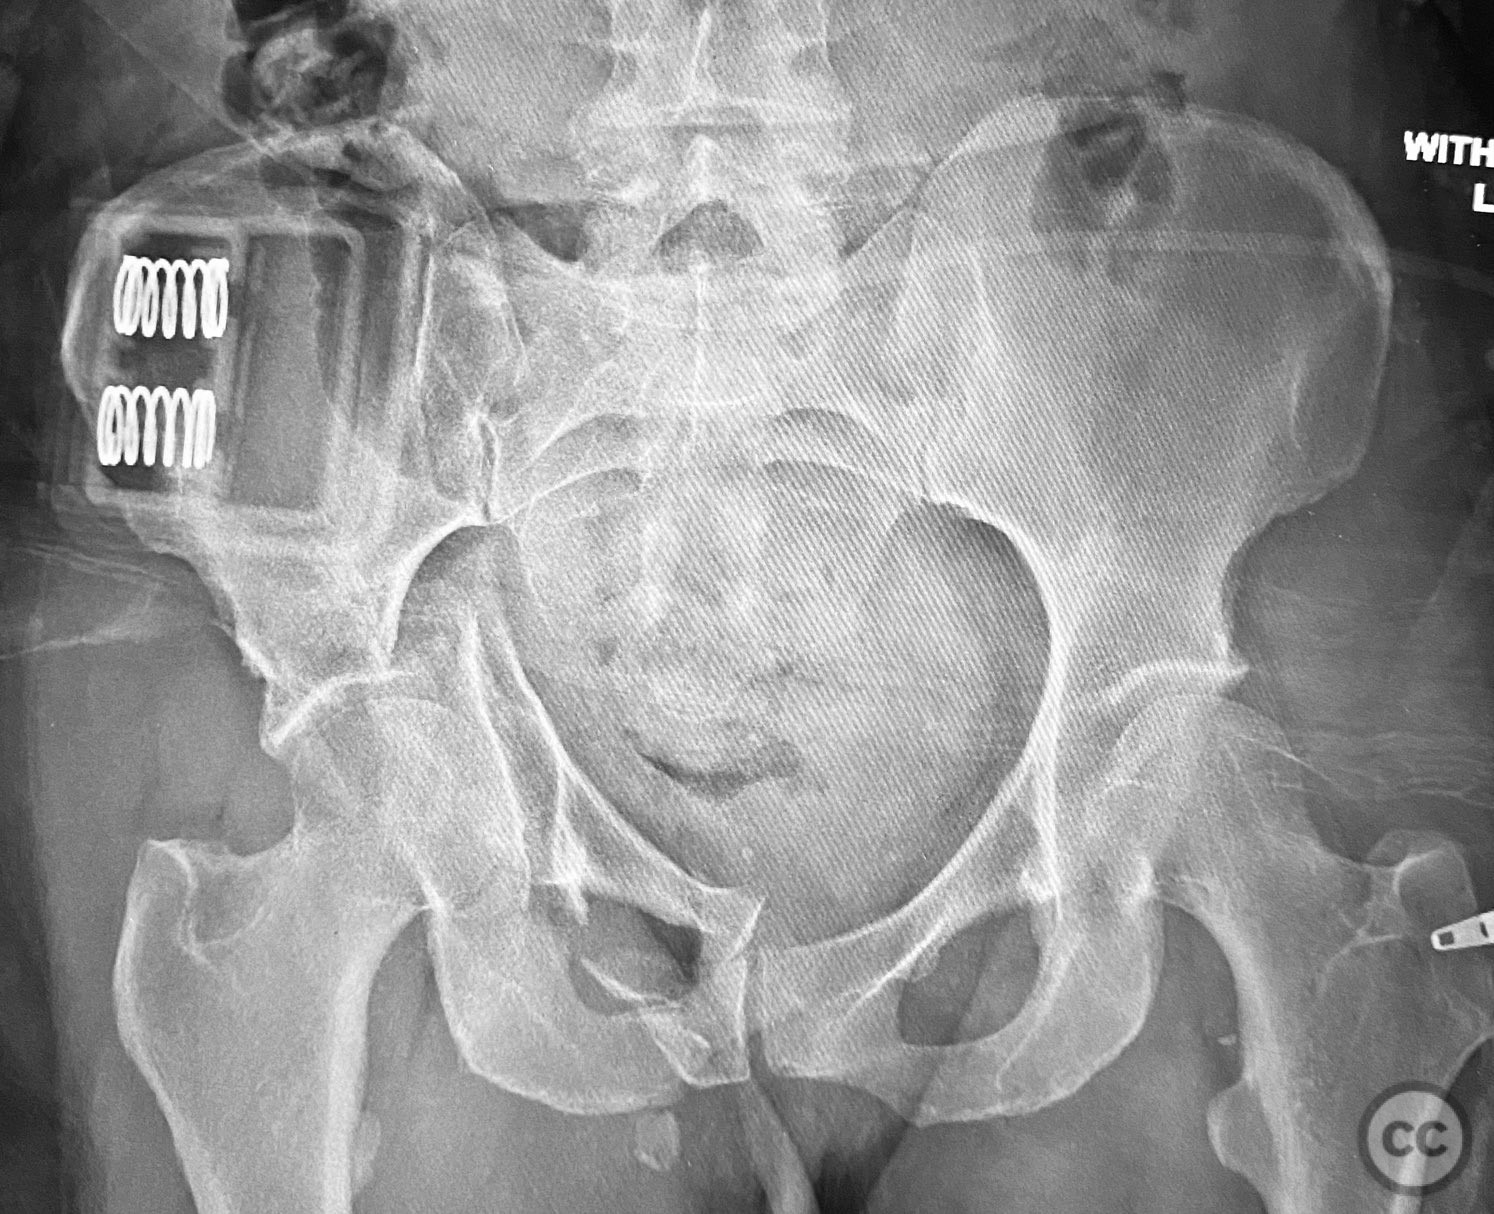

Uploaded on Sep 12 2025

Early Percutaneous Stabilization of Complex Pelv...

• Case by Chip Routt

Specialist Consultant - United States